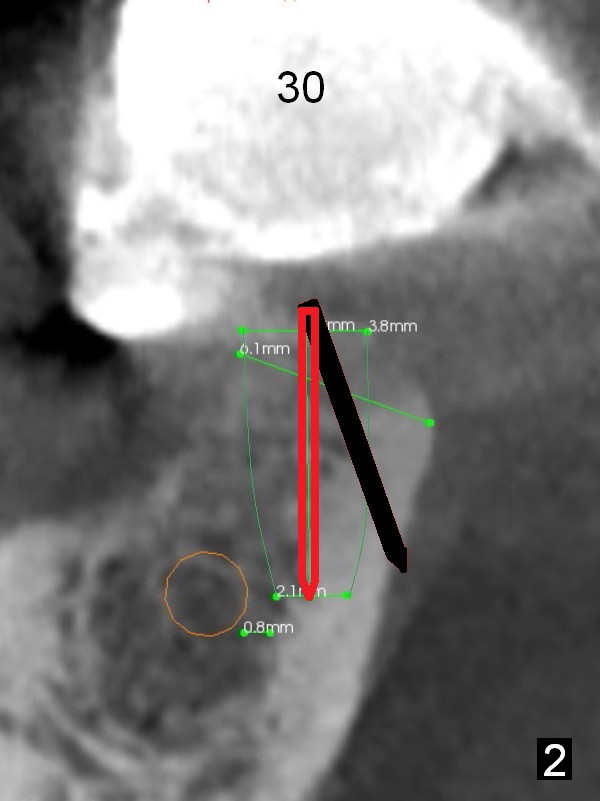

At the site of #30, the lingual plate perforates in the early stage of osteotomy (Fig.1 red arrow). As indicated by the thick lingual plate, the osteotomy turns out to be difficult. The trajectory is corrected immediately (Fig.2 red) and with control so that the Inferior Alveolar Canal (brown circle) will be not be violated. The perforation is repaired with Osteogen plug (Fig.3 white) and nearby autogenous bone (red circles) before placement of a 3.8x8 mm implant (green).